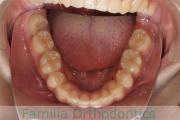

- ≫治療後

上顎

下顎

前歯の関係など

右側

正面

左側